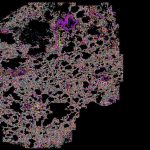

This is a spatial transcriptomic deconvolution of healthy & diabetic glomeruli.

Courtesy of Drs. Ricardo Melo Ferreira & Michael Eadon at WUSTL TMC.